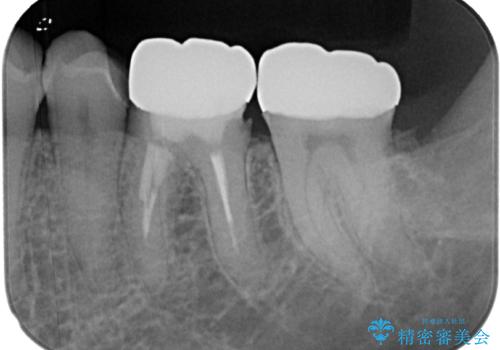

詰め物の範囲が大きいためフルジルコニアクラウンによる補綴治療を行いました。

拡大鏡視野下で詰め物、虫歯を除去しフルジルコニアクラウンに適切な形に整えました。

型どりの際には唾液も多く舌も動いてくるため個歯トレーにて精密印象を行っています。

仮歯に変える前に左下の埋伏親知らず抜歯を行っています。